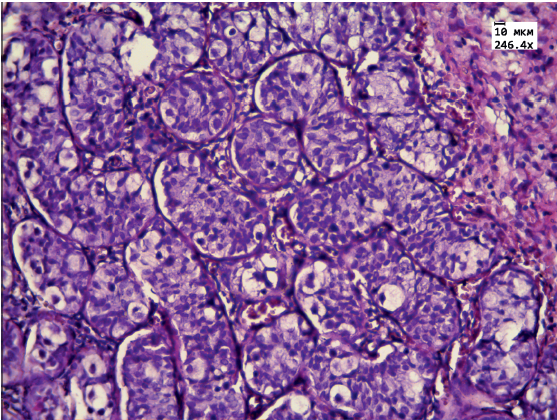

Гистологическое исследование интраоперационного материала гонад показало наличие ткани яичка и яичника, разделенных фиброзной прослойкой. Ткань яичника фиброзирована, деление на корковый и мозговой слой нечеткое. В корковом слое определяются примордиальные фолликулы с выраженными дистрофическими изменениями (рис. 1, на цв. вклейке). Ткань яичка разбита на дольки фиброзными прослойками, единичные микрокальцинаты. В эпителии канальцев резко выраженные дистрофические и пролиферативные изменения: увеличение размеров клеток, ядер, гиперхромия ядер. Клетки сперматогенного эпителия располагаются хаотично и находятся в разной степени зрелости. Обращают на себя внимание крупные клетки с четко определяемым ядром и наличием в нем ядрышек — половые клетки (рис. 2, на цв. вклейке). Такое строение сперматогенного эпителия соответствует организации, характерной для антенатального периода [4].

Рис. 2. Микроскопическая картина ткани яичка: эпителий канальцев незрелый, с дистрофическими и пролифера- тивными изменениями. Окраска гематоксилином и эозином, ув. 250.

Результаты гистологического исследования гонад нашего пациента показали наличие незрелой тестикулярной ткани с выраженными пролиферативными изменениями, микрокальцинатами. В ткани яичника отсутствовало четкое деление на корковое и мозговое вещество. Примордиальные фолликулы, определяемые в овариальной части гонады, имели выраженные дистрофические изменения. На основании этих данных было принято решение о проведении гонадэктомии.